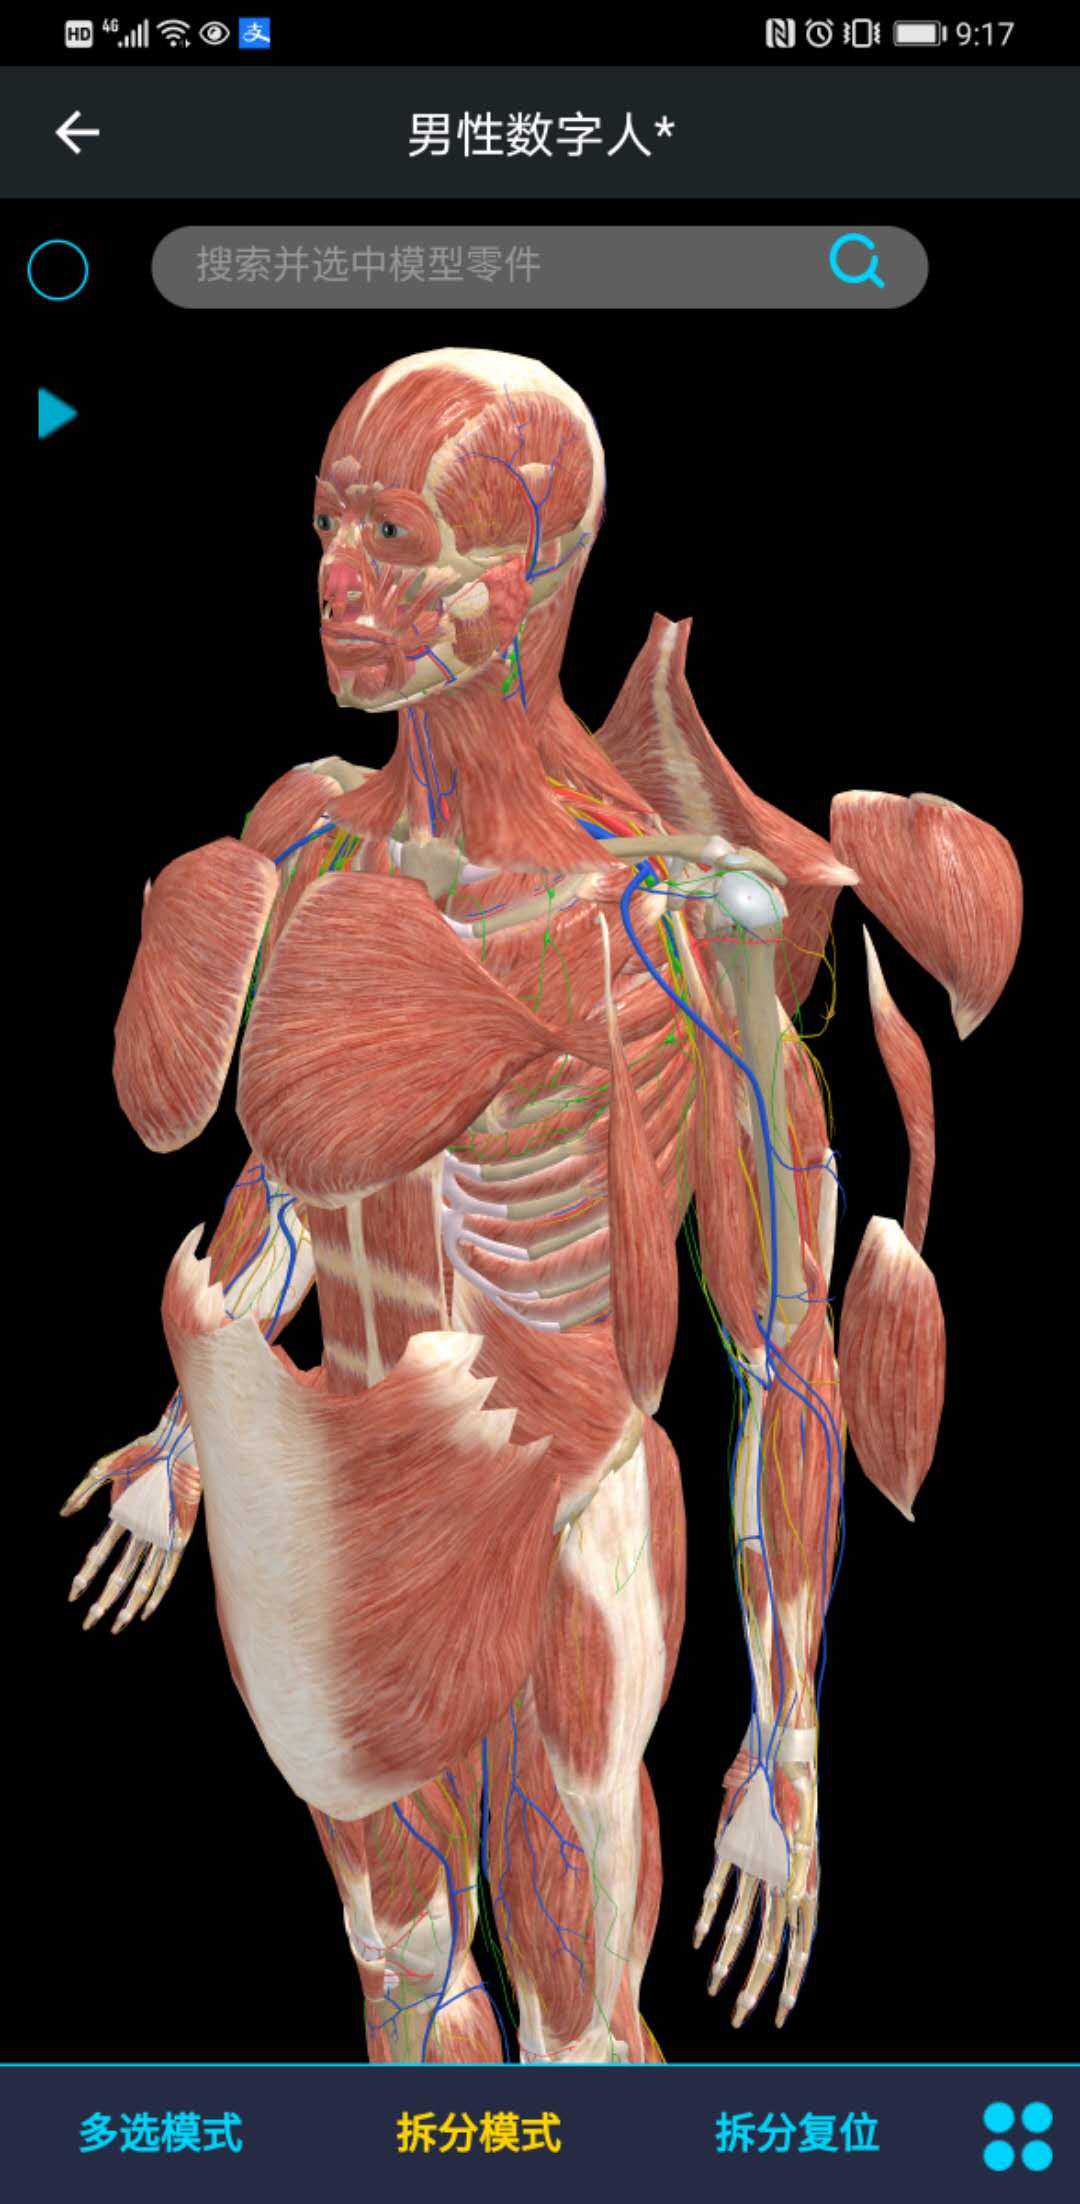

医维度人体解剖软件是一款专为医学教育和临床学习设计的高精度三维人体解剖软件,它提供了详尽的人体结构展示和互动学习功能,帮助用户深入理解人体解剖知识。

该软件结合了最新的三维建模技术和医学影像学数据,确保所有解剖结构的高精度还原,为用户提供逼真的学习体验。

许多用户称赞该软件的三维模型精细度高,能够清晰地展示人体各个部位的细节结构,有助于深入理解解剖知识。

软件内置的互动学习功能,如旋转、缩放、标注等,让用户能够自由探索人体结构,增强了学习的互动性和趣味性。